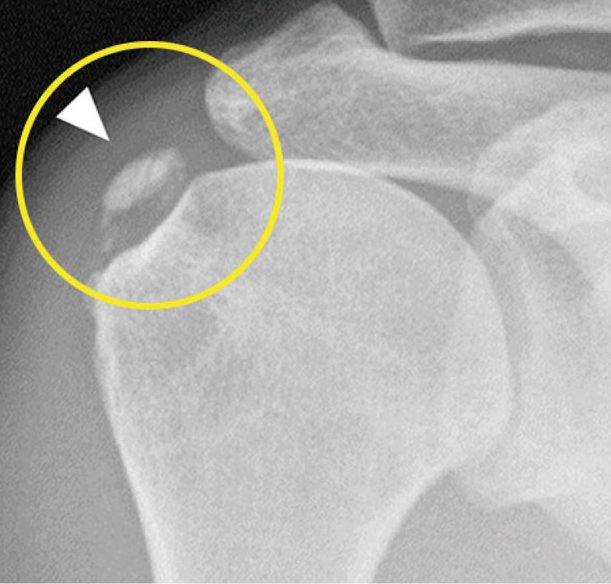

석회화 건염이라고도 하는 어깨 석회화는 발생하면 통증이 심할 수 있습니다. 이 질환은 어깨 힘줄에 칼슘 침착물이 형성되어 불편함, 경직, 이동성 제한을 유발합니다. 이 질환은 놀라울 정도로 흔하며 모든 연령대의 사람들에게 영향을 미치지만 30세에서 60세 사이의 성인에게 자주 발생합니다. 이 질환에 대해 잘 모른다면 복잡하게 들릴 수 있지만 어깨 석회화의 원인, 증상 및 치료법에 대해 공부하고 이해하면 효과적으로 관리하는 데 도움이 될 수 있습니다. 또한 증상 개선을 위해 이 질환이 악화되는 것을 막고 치료하는 데 도움이 될 수 있는 몇 가지 영양제도 살펴볼 것입니다.

어깨 석회화는 팔을 움직이는 회전근개 근육의 힘줄에 칼슘이 축적되면 발생합니다. 현재 이러한 축적의 정확한 원인은 완전히 명확하지는 않지만 몇 가지 요인이 그 원인으로 작용합니다. 석회화 건염의 영향을 받는 대부분의 사람들은 30~60대입니다. 어깨에 부담을 주는 특정 스포츠나 직업의 움직임과 같은 반복적인 움직임도 이 질환을 유발할 수 있습니다. 또한 당뇨병이나 대사 문제와 같은 건강 문제도 위험을 증가시킬 수 있습니다. 칼슘 침착물이 형성됨에 따라 주변 조직을 자극하여 통증과 염증을 유발할 수 있습니다. 일반적인 증상으로는 특히 움직임에 따라 어깨에 날카롭거나 따끔거리는 통증과 제한된 범위의 움직임이 있습니다. 통증으로 인해 붓기, 팔의 쇠약, 심지어 수면의 어려움을 느낄 수 있습니다. 단순한 작업을 수행하기 어려울 정도로 심한 통증을 경험하는 사람들도 있으므로 이러한 징후를 발견하기 시작하면 심각하게 받아들이고 치료를 서둘러 받는 것이 중요합니다.